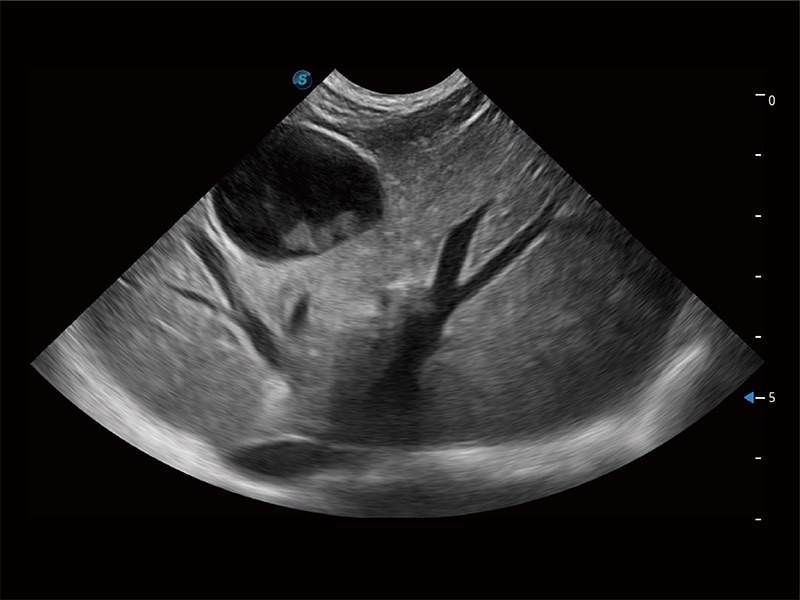

ProPet 80 配备了丰富的心脏探头群、先进的成像技术和专业的心脏测量工具,可帮助动物医生为不同体型和生理结构的动物提供心脏和心肌功能的全面评估。